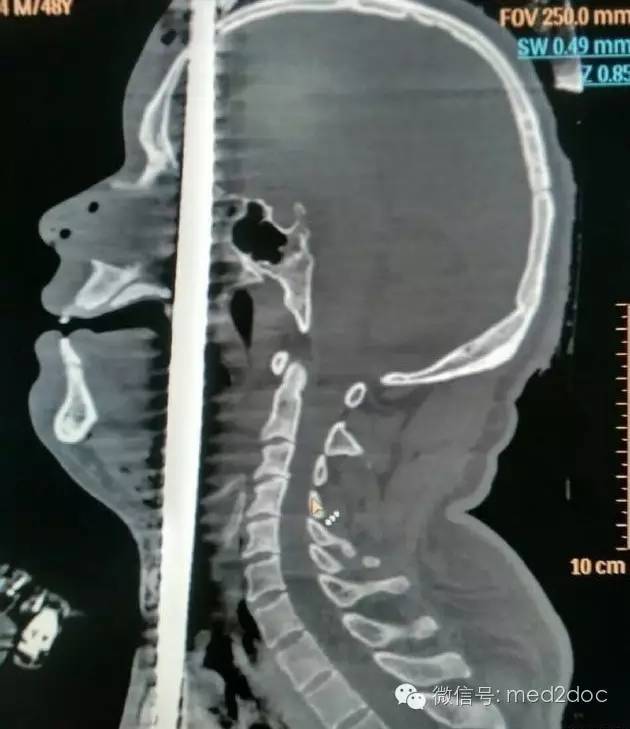

据齐鲁医院报道,最近约30名专家联手执刀,历时7个小时……成功救治1例1.5米钢筋从阴部贯穿头顶的贯通伤,患者奇迹生还。

6月14日下午3点多,济南一名中年男子从5米高空坠落,地上正好有一竖起的钢筋,这根钢筋从男子的阴部直穿头顶。患者是由一根粗约1.5厘米的钢筋从阴部直插穿头顶,阴部以下露出长约四十厘米的钢筋,头顶上穿出长约五十厘米的钢筋,男子*体下**和脸部都留着鲜血,场面触目惊心。

经过CT等全方面检查后,确定钢筋已贯穿男子的泌尿、腹部、胸部、口腔、鼻腔、脑部等具体部位。钢筋从男子的右阴囊插入,途径泌尿系统,伤及腹部的肝脏,紧贴颈动脉贯穿而过。从咽喉直插入口腔,伤及舌头,从上颚经鼻腔,插入大脑,钢筋从头顶穿出。